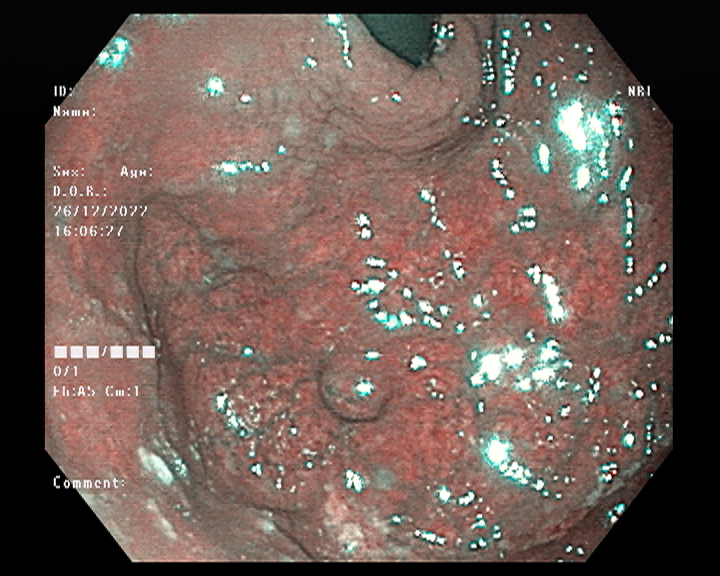

Endoscopy and colonoscopy are safe and accurate procedures used to directly examine the digestive tract and detect the root cause of chronic acidity, GERD, abdominal pain, bleeding, and bowel irregularities. These minimally invasive tests help identify ulcers, inflammation, infections, polyps, strictures, and early cancerous changes.

At Sapphire Gastroenterology Center, modern endoscopic equipment ensures precise diagnosis and, when required, therapeutic intervention during the same procedure. Based on findings, targeted treatment plans are created, including medication, diet guidance, and preventive strategies. Early diagnosis through endoscopy and colonoscopy plays a crucial role in preventing serious complications and improving long-term digestive health.